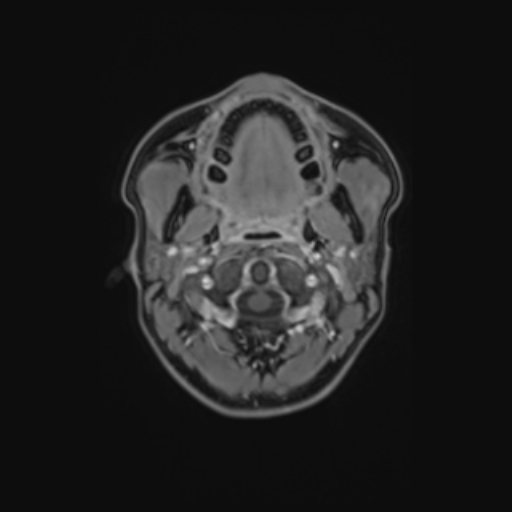

Esame: RM ENCEFALO MDC del 24-03-2026

Descrizione Serie: pd+t2_tse_tra_p2

Modalità: MR